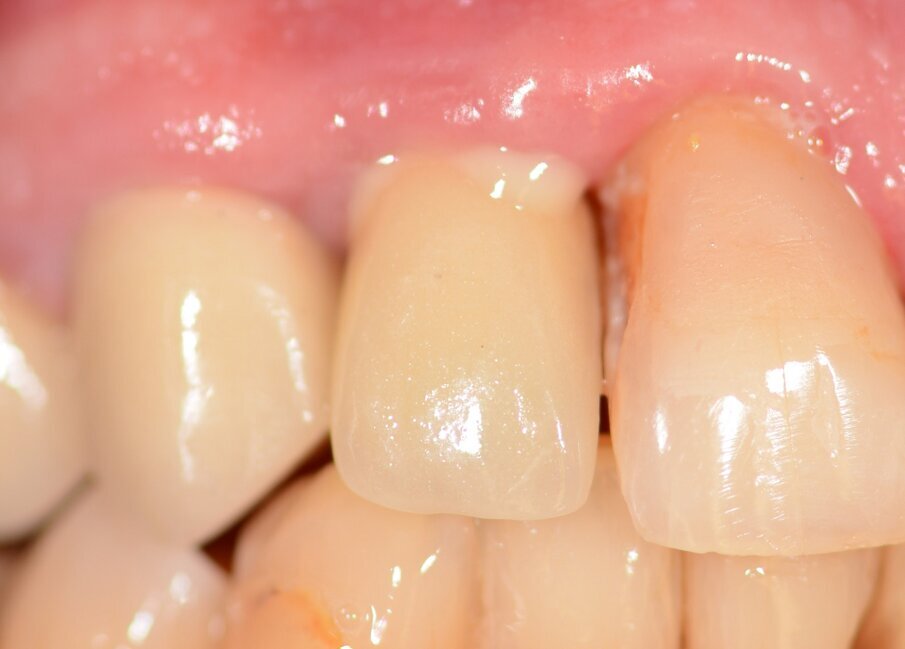

The implant apicectomy in Case 3 shows that one year after the immediate implantation with immediate loading there was inflammation around the implant apex. The rest was properly integrated (Figs. 13–20).

Fig. 13: Initial situation. Visible fistula one year after loading.

Fig. 14: Bone defect of 9.27mm in diameter.

Fig. 16: Granulation tissue removal with Er:YAG.

Fig. 17: Implant resection.

Fig. 20: Situation 1.5 years post-op. No sign of inflammation.